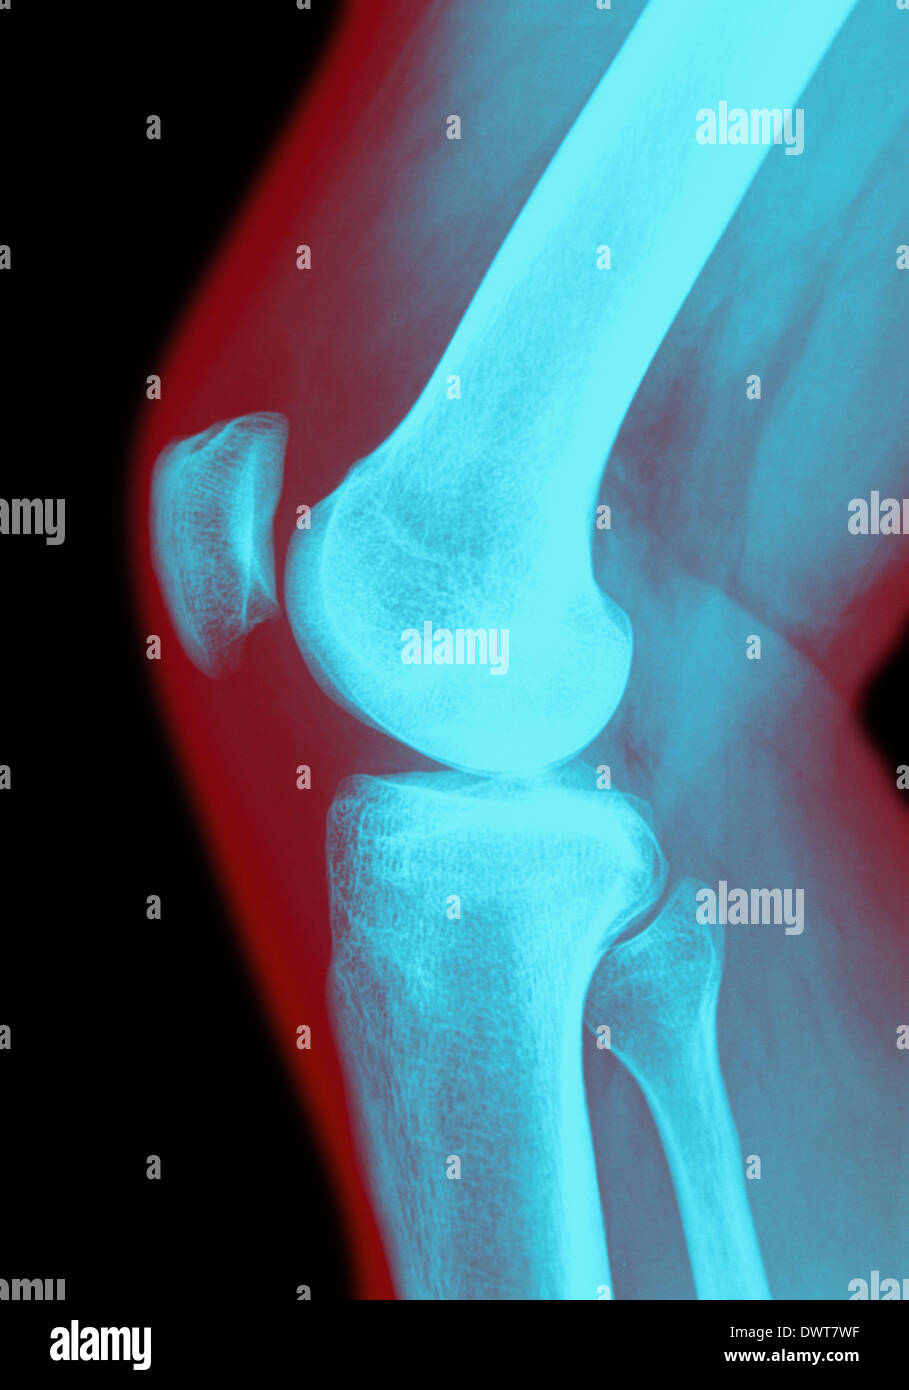

From www.alamy.com

Knee x ray Stock Photo Alamy Knee X Ray Guidelines The history and physical examination, which are necessary to develop a differential diagnosis prior to the selection of. There are several guidelines for the appropriate imaging of patients presenting with knee pain. It consists of 5 criteria highly correlated with knee fracture status. Identifying the type and severity of the condition is important for effective management. Knee X Ray Guidelines.